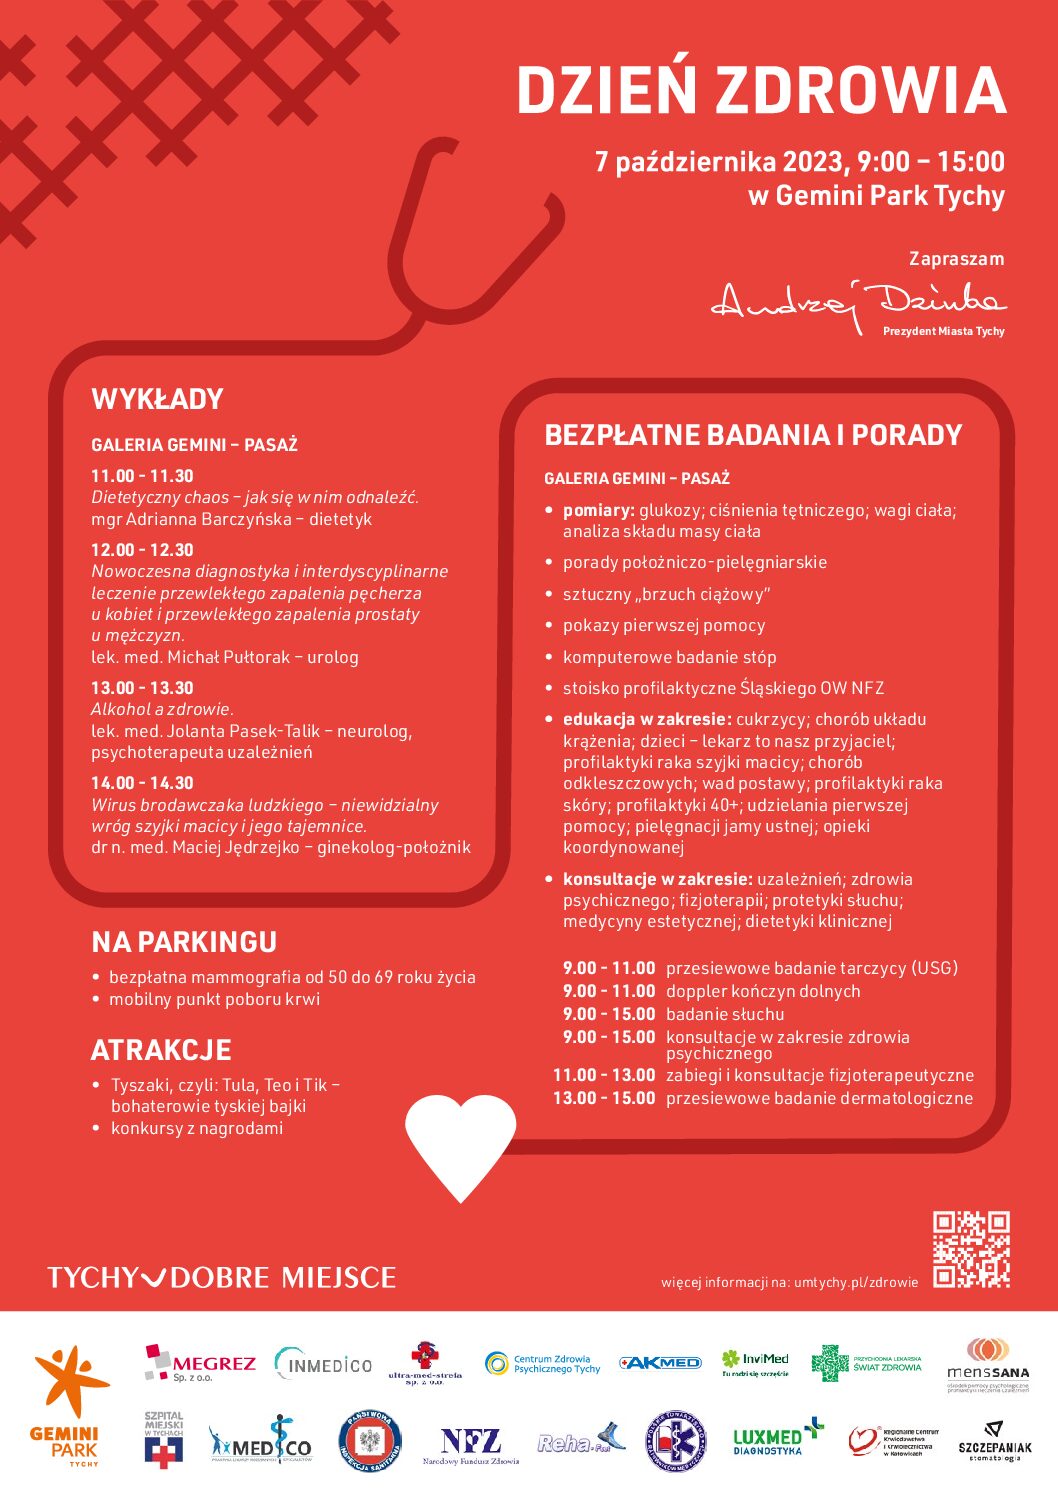

paź 09, 2023

Dzień Zdrowia już za nami

Dziękujemy wszystkim za wzięcie udziału razem z nami w Dniu Zdrowia w…